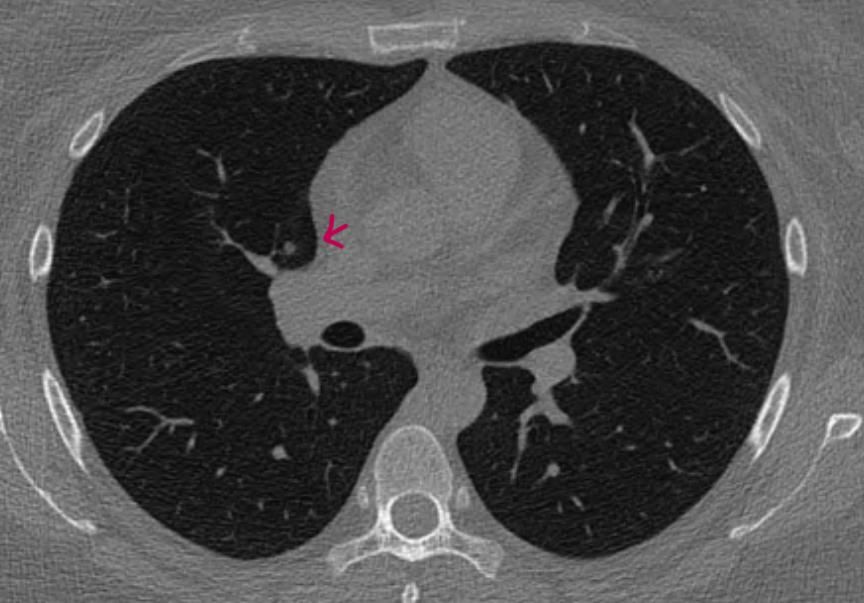

폐결절 간유리인가요 반고형 간유리인가요, 고형인가요

첫병원은 어느슬라이드에서는 고형같기도하지만 간유리같다.지금 큰병원은 처음엔 간유리랫는데 영상의학과 판독후 고형이라고 나온후 두번째 병원도 갑자기 고형이래요.

슬라이드 하나넘길때마다 아주옅은 간유리에서 음영짙은 결절에서 또 넘기면 완전 하얀 고형처럼 보여요.

파란색, 붉은색 화살표 표시있는게 시리즈5 1thk인데

시리즈 2인 3thk만 보면서 진료를 받은거 같아요. 파란색 사진의 고형도 안나오고,

빨간색 사진의 짙음 음영 고형?반고형?간유리 결절이 안보이는 ct영상